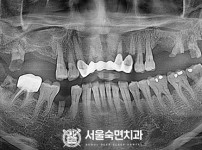

임플란트-전후사진1